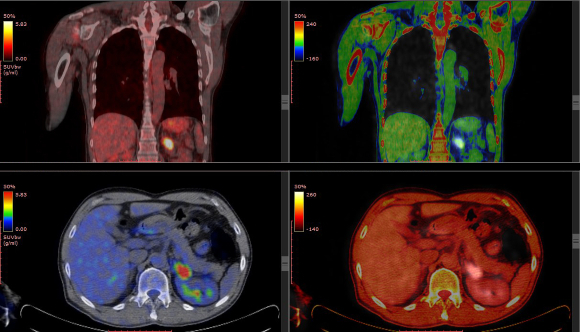

PET (קיצור של Positron Emission Tomography) היא שיטת דימות שמסוגלת לעקוב אחרי תהליכים פיזיולוגיים שונים באמצעות שימוש בחומר רדיואקטיבי. בניגוד לשיטות דימות כגון צילום רנטגן, שמספקות מידע על תקינות מבנית של הרקמה הנבדקת, דימות PET מסוגל לתת מידע על תקינות תפקוד הרקמות.

כדי לבצע דימות של תהליך ביולוגי מסוים ב-PET מזריקים לנבדק סמן ("טרייסר"). הסמן יכול להיות סוכר, חלבון, הורמון או כל תרכובת כימית אחרת המשתתפת בתהליך הביולוגי אחריו מעוניינים לעקוב. הסמן המוזרק מכיל אטום רדיואקטיבי, כך שכאשר הוא מגיע למקום בגוף שבו הוא אמור למלא את תפקידו, אפשר למצוא את מיקומו. מציאת מיקום הסמן מבוססת על כך שהגרעין של האטום הרדיואקטיבי בסמן אינו יציב. חוסר יציבות זה גורם לאטום הרדיואקטיבי לפלוט חלקיק בשם פוזיטרון, בעל מסה זהה לאלקטרון, אבל מטען חיובי, בניגוד לאלקטרון השלילי. כאשר פוזיטרון פוגש אלקטרון, סמוך למקום היווצרותו, נפלטים גלים אלקטרומגנטיים לשני כיוונים מנוגדים ונקלטים בגלאי שהנבדק שוכב בתוכו. מחשב המנתח את הגלים הנקלטים מרכיב תמונה תלת מימדית של מיקום הסמן הרדיואקטיבי בגוף הנבדק. אחד הסמנים הנפוצים ביותר בדימות PET הוא FDG, גרסה שונה מעט של הסוכר גלוקוז. הוא משמש לסימון רקמות בעלות ספיגה וצריכה גבוהה של גלוקוז, מאפיין בולט של גידולים סרטניים.

רופאים עושים שימוש נרחב ב-PET לצורך איתור גידולים סרטניים, אבחון מחלות במוח ותכנון ניתוחי ראש, תכנון ניתוחי מעקפים בלב, אבחון וטיפול במחלות זיהומיות ועוד. אפשר להשתמש ב-PET גם בתהליך פיתוח תרופות חדשות כדי לבחון את התפשטות התרופה בגוף וקצב ספיגתה, או למחקרים אחרים. פעמים רבות נעשה דימות משולב של PET ו-CT כדי לקבל מידע מקיף אודות הנבדק.

כמות הקרינה שאליה נחשפים בבדיקת PET דומה לכמות בבדיקת CT (כמובן שהכמות המדוייקת תלויה במאפיינים המדוייקים של הבדיקה). הסמן הרדיואקטיבי מפסיק לפלוט פוזיטרונים תוך שעות אחדות מרגע ייצורו.

בדיקה רדיואקטיבית המאפשרת לבחון תפקוד רקמות. גו של אדם בסריקת PET, מבט מאחור (למעלה) ומלמעלה | צילום: springsky, Shutterstock